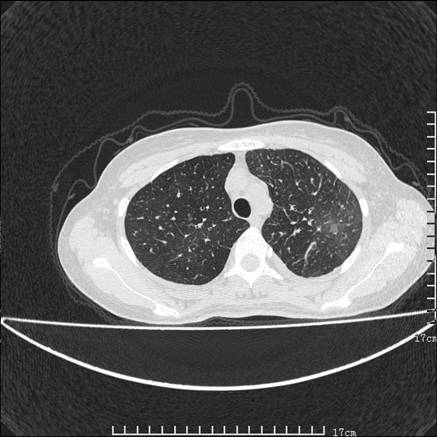

女,46岁,患胃溃疡多年,溃疡大小约1.0cm左右,后于5年前手术,病理为胃癌。主诉:半月前感冒后胸闷,气短,有咳嗽,无明显咳痰,无发热。偶有腰背部不适。

以下为高分辨扫描图像

鉴别:

1、结节病,多位于肺的上中部和后部,呈向心性分布,造成近肺门区的支气管血管束周围间质和胸膜下间质增厚,小叶间隔增厚不明显,即使增厚也较为局限

2、尘肺,可以通过病史,肺外周为主的多发结节,胸膜假斑,聚合成的团块,间质纤维化等鉴别

3、肺水肿,肺水肿可以造成肺间质的增厚,为光滑的增厚且常为双侧对称性分布。

支持 肺间质性肺炎,不除外癌性淋巴管炎,建议抗炎治疗复查---------小叶间隔增厚,磨玻璃影及片絮状影